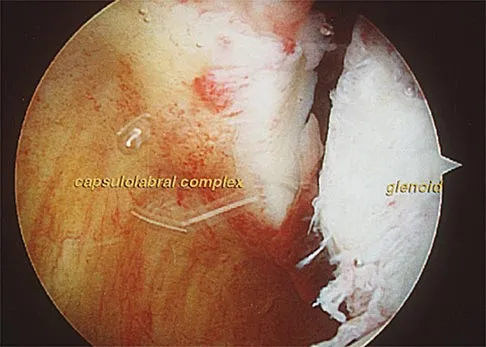

A 51-year-old male truck driver has had progressive left hip pain for more than 2 years, and he reports that the pain has become severe in the past 9 months. He is now unable to work because of the pain. Examination reveals that range of motion of the hip is limited to 95 degrees of flexion, 0 degrees of internal rotation, and 20 degrees of external rotation. The plain radiograph, MRI scan, and intraoperative gross photographs are shown in Figures 9a through 9d. Management should consist of